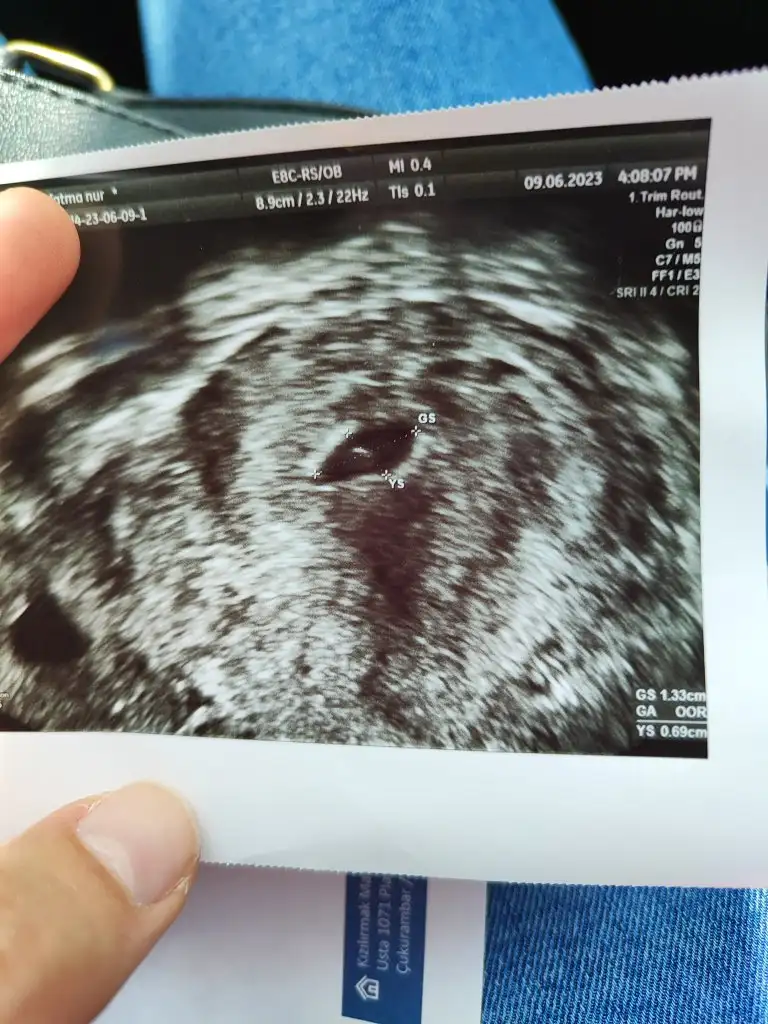

Gözün aydın canımKızlar doktordan çıktım yolk ve keseyi gördük çok şükür kalp atışı için 10 gün sonra gel garanti olsun dedi istanbuldaki doktoruma gidecegim inşaallah.Mindamin senin dediğin gibi yaptı hesabı 5 buçuk haftalık sesi transferin üstüne 12 gün ekledi

Ne güzel bir görüntü bu maşallah bebişeKızlar doktordan çıktım yolk ve keseyi gördük çok şükür kalp atışı için 10 gün sonra gel garanti olsun dedi istanbuldaki doktoruma gidecegim inşaallah.Mindamin senin dediğin gibi yaptı hesabı 5 buçuk haftalık sesi transferin üstüne 12 gün ekledi

Kızlar doktordan çıktım yolk ve keseyi gördük çok şükür kalp atışı için 10 gün sonra gel garanti olsun dedi istanbuldaki doktoruma gidecegim inşaallah.Mindamin senin dediğin gibi yaptı hesabı 5 buçuk haftalık sesi transferin üstüne 12 gün ekledi